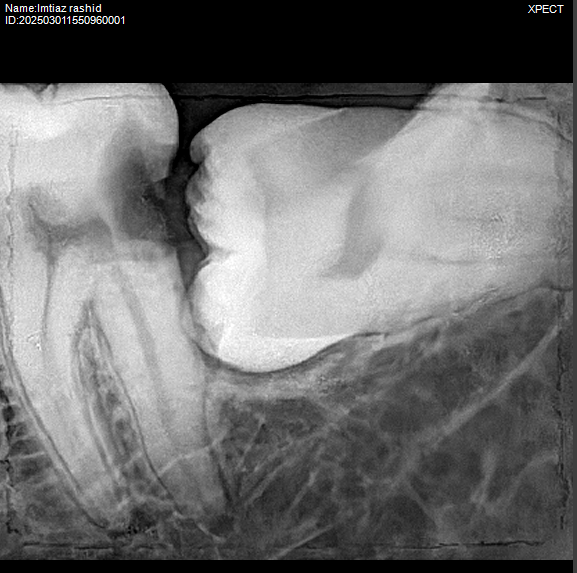

Wisdom tooth extraction is a common procedure to remove one or more third molars, typically located at the back of the mouth. These teeth often cause problems because they may not have enough room to emerge fully or may grow at an angle, becoming impacted. Impacted wisdom teeth can lead to pain, infection, or crowding, affecting surrounding teeth.

Wisdom teeth often cause problems due to lack of space, impaction, or growing at odd angles, leading to pain, infection, or crowding.